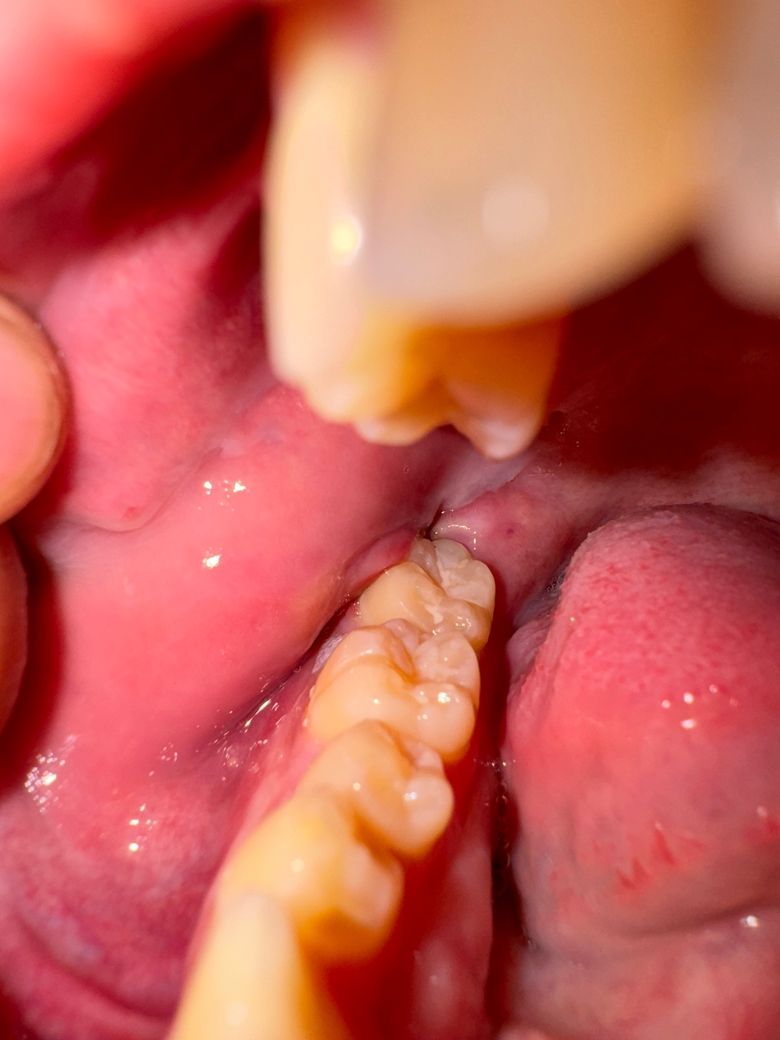

사랑니 발치후 일주일차 상태 괜찮은건가요?

턱은 아직 안벌려지는 상태고 입 안은 이 상태인데 안쪽 붓기도 좀 있는편이고 아무것도 뭐가 뭔지 잘 모르겠어서 괜찮은편인가요?ㅠㅠㅠ

보여주시는 사진 만으로는 정확한 검진은 어려우나 봉합하 발사까지 진행한 상태로 보입니다. 발치한 부위에는 아직까지는 발치와가 치유중인 상태로 어두운 공간이 보이는 상태입니다.

사진상으로는 점막의 색이나 성상 등은 정상적인 치유과정 상태이있는것으로 보이며 개구제한은 부종 및 크게 개구하고 발치한 뒤 발생할 수 있는 합병증으로 천천히 개구하는 연습 하시며 운동을 해주시면 금방 완화됩니다.

만약 통증이 심해지거나 붓기가 점점 더 심해진다면 이는 감염이 된 상태이므로 즉시 병원 내원하시기를 바랍니다.